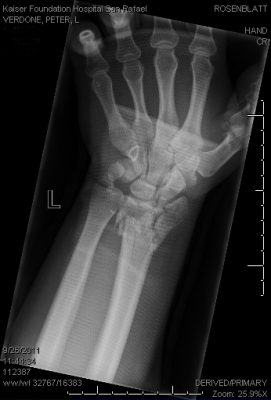

verdone pre op AP